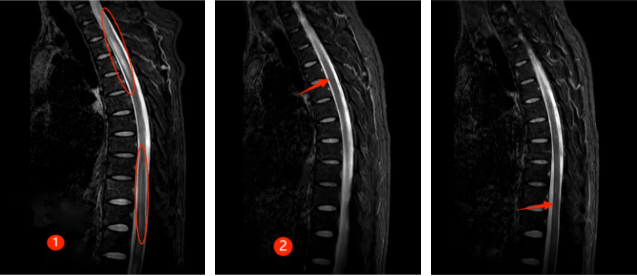

半年前,30来岁的谭先生突然出现颈肩部疼痛不适及肢体麻木,此后短短数天迅速出现四肢瘫痪及大小便失禁,生活不能自理。正值风华正茂的年纪,谭先生一时无法接受,心急如焚的父母带着吓坏了的谭先生来郑州大学第五附属医院就诊,入住神经内科二病区。入科时患者已四肢全瘫,紧急完善相关检查,发现患者脑干、颈髓、胸髓、腰髓广泛病变(见图①),随后完善腰穿及相关抗体检查,最终确诊为MOGAD。

经过及时的免疫治疗,患者病情逐渐好转,出院时患者已能下床行走,再次拾起对生活的信心,复查磁共振,患者脑干、颈髓、胸髓、腰髓的病变已明显好转(见下图②)。半年后随访,患者已恢复正常的生活,预后非常好。